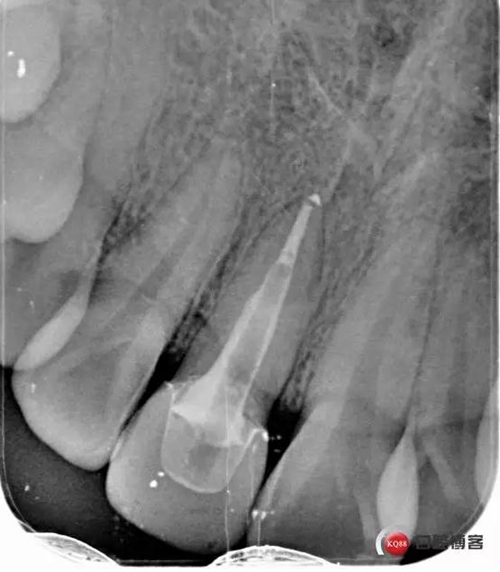

術(shù)后牙片可以看出樁的長(zhǎng)度有明顯增加。到達(dá)預(yù)備長(zhǎng)度。術(shù)后齦緣高度與鄰牙一致